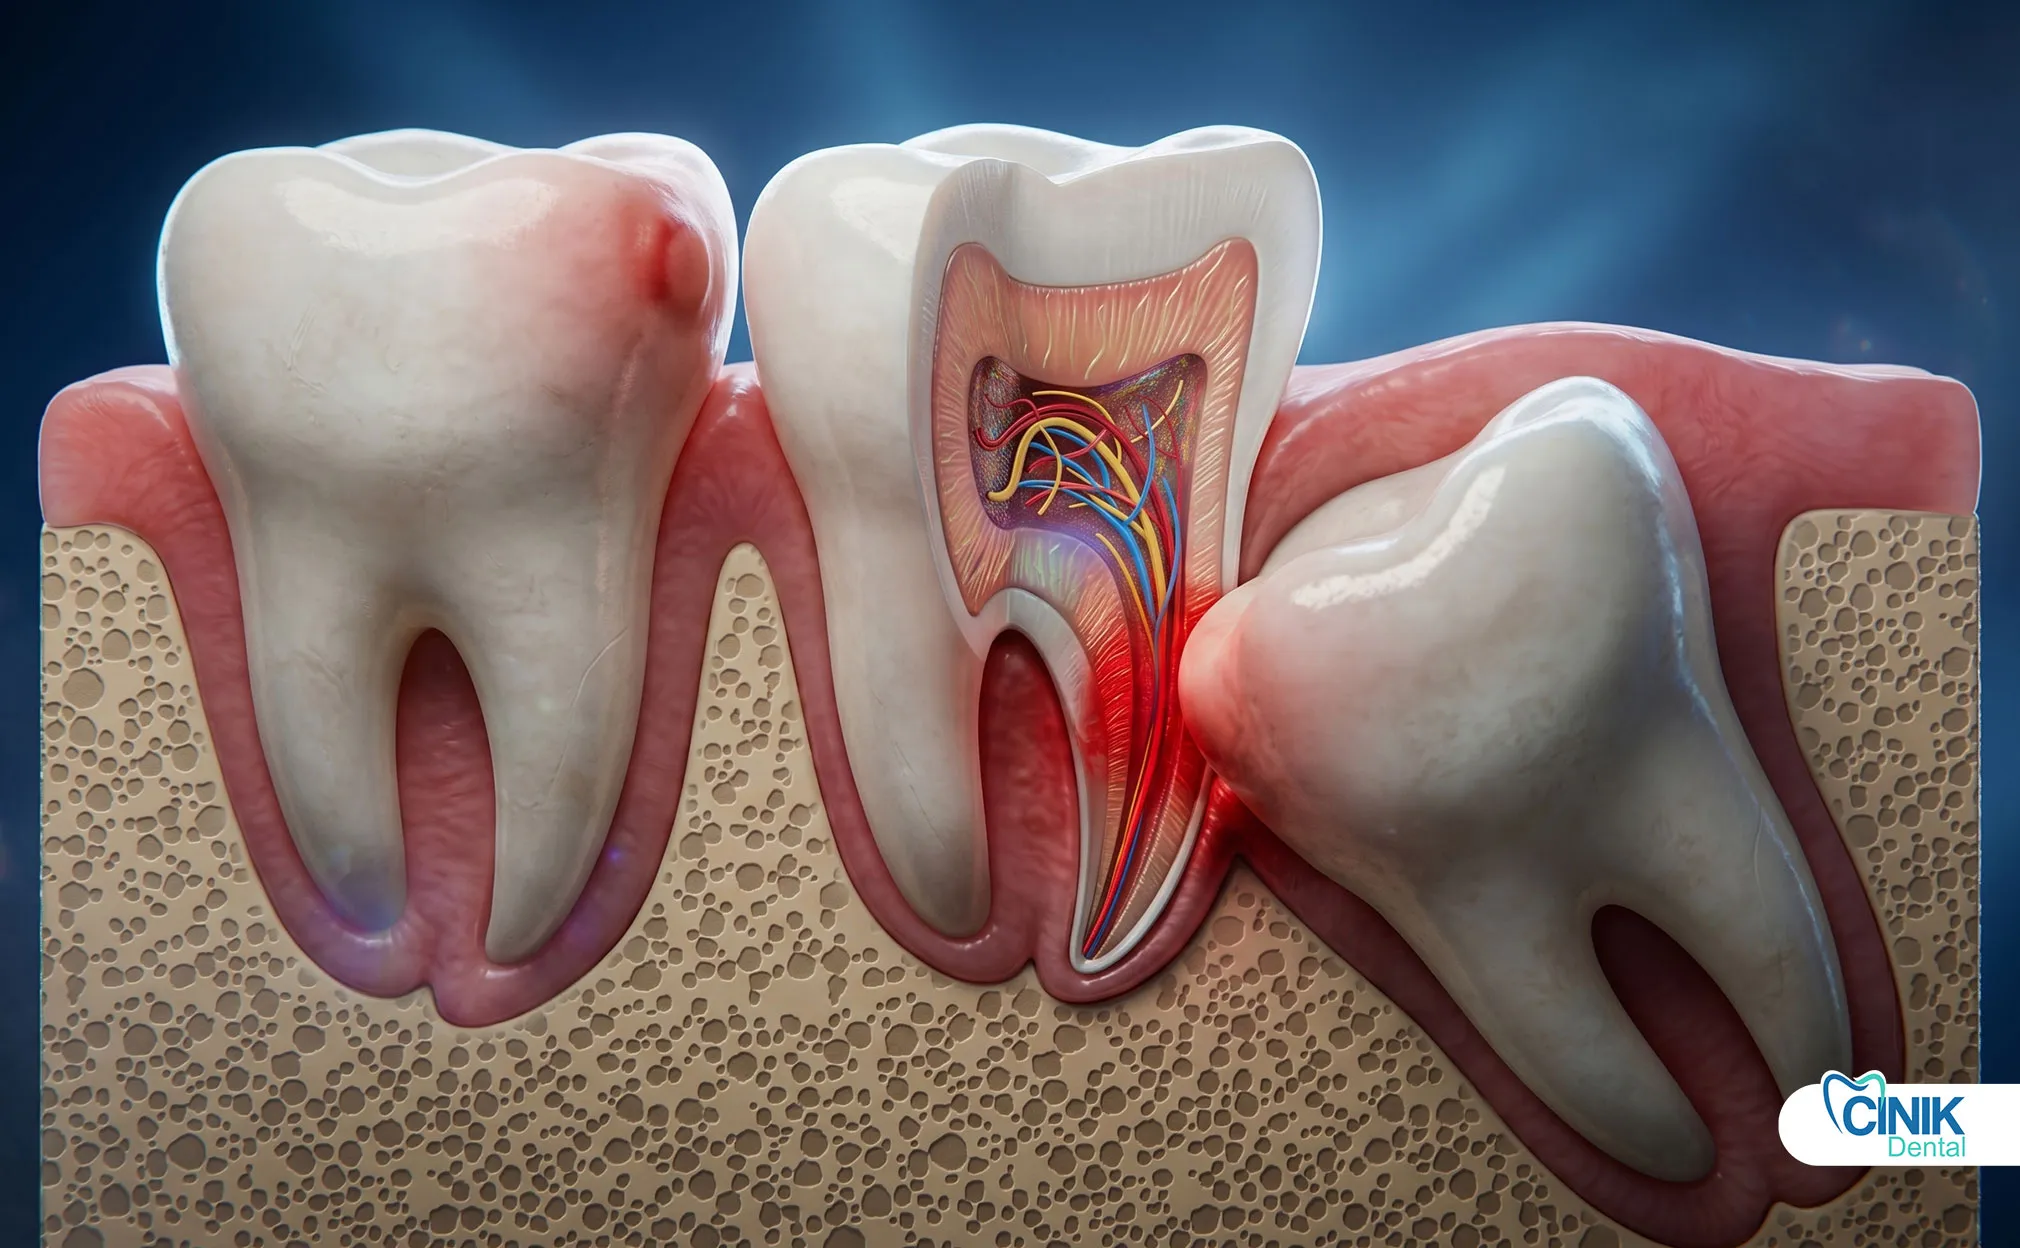

Cysts and tumors: Dentigerous cysts associated with impacted third molars may cause significant bone destruction if untreated. The incidence of cystic change ranges from 0.5% to 3% per impacted tooth (Matzen et al., 2019).

Root resorption of adjacent teeth: External resorption of second molar roots by impacted third molars represents an absolute indication for immediate extraction.

Periodontal disease risk: Retained third molars create inaccessible periodontal pockets distal to second molars. Studies demonstrate that extraction improves periodontal health in adjacent teeth (Kugelberg et al., 2020).

Caries risk: Partially erupted wisdom teeth develop caries at rates exceeding fully erupted teeth due to hygiene challenges. Additionally, mesioangular impactions promote caries on distal surfaces of second molars.